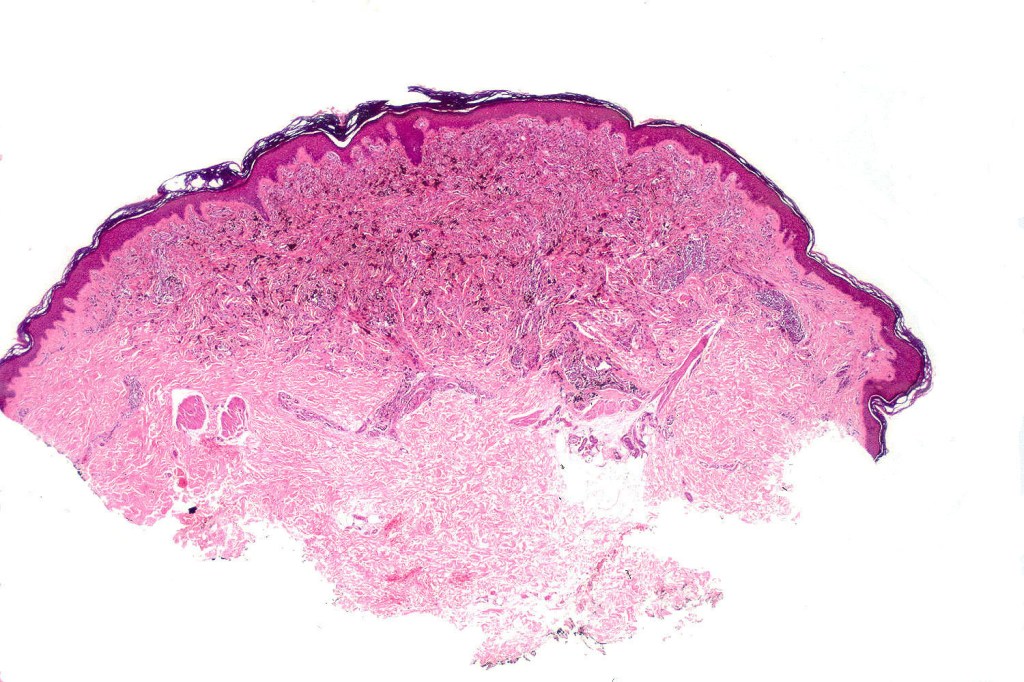

Cellular blue nevus

This uncommon most often devlops on the buttocks, sacrococcygeal region & distal extremities although it may be seen at just about any site. It shows a predilection for females and is diagnosed most often in the 2nd-4th decade. It presents as a blue-black/ or black nodule measuring 1-2 cm in dianeter. Similar to common blue nevus, the cellular variant can be encountered in a wide range of non-cutaneous locations.

Histological features

•Most characteristic is the dumbbell silhouette although a plague morphology may also be encountered

•Combined nevus variant

•Admixture of spindle cells, pigmented bipolar or dendritic cells & melanophages

•Cytoplasm is pale and nuclei are small with inconspicuous nucleoli

•An alveolar pattern is characteristic particularly with clear cell nodules

•Mitoses are typically very sparse or absent

•No atypical mitoses

•No Necrosis or lymphovascular invasion

•Multinucleate giant cells sometimes present

•Stromal fibrosis, myxoid change, vascular hyalinization with cyst formation are often seen

•Some tumors are composed spindle cells in a fascicular or neuronevoid pattern

•Perineural involvement may be seen

•Balloon cell change

•Desmoplastic variant

•Hypopigmented variant